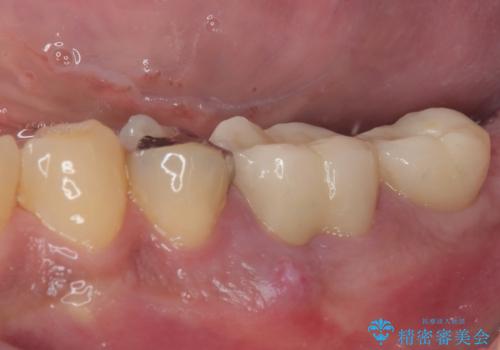

治療は順調に進み、わずか3ヶ月でセラミッククラウンを装着することができました。

他の歯への影響もなく、無事に治療を終えることができました。